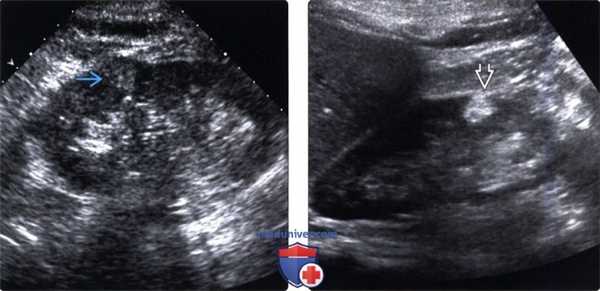

(Левый) На продольном ультразвуковом срезе в среднем отделе правой почки визуализируется солидное гомогенное, немного гиперэхогенное новообразование, представляющее собой метастаз меланомы, который невозможно отличить от почечноклеточного рака (ПКР).

(Правый) На соответствующем УЗ срезе с цветовой допплерографией визуализируется отсутствие выраженного кровотока внутри образования. Несмотря на то, что данные серошкального исследования неотличимы от ПКР, метастазы, по сравнению с ПКР обычно более гиповаскулярны.

(Левый) На ультразвуковом срезе с цветовой допплерографией визуализируется крупный, гиперэхопенный, гиповаскулярный метастаз в почке. Контуры почки не изменены. Почечные метастазы обычно меньше и менее гиперэхогенные, а также хуже выявляются при ультразвуковом исследовании.

(Правый) На продольном УЗ срезе визуализируется увеличенная, шаровидная почка с гипоэхогенной инфильтрацией коркового вещества при множественной миеломе. Обратите внимание на относительно интактную почечную пазуху.